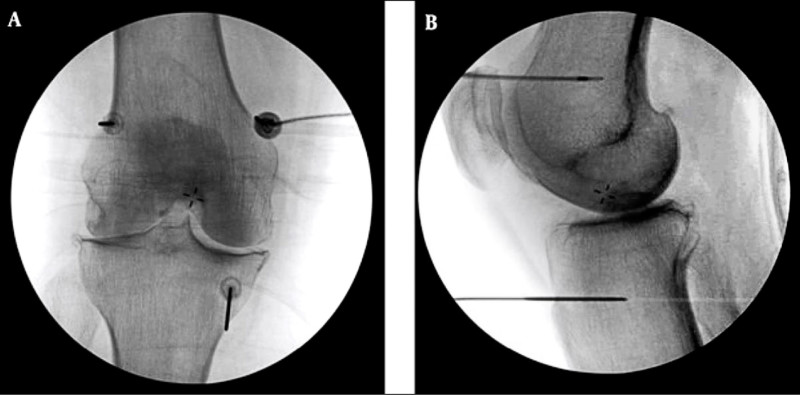

李宜軒表示,針對不適合手術或不願意手術的患者,可採「高頻熱凝療法」止痛,執行方式是在局部麻醉下,以X光定位將電極導針導引至膝蓋的3個主要感覺神經叢,確認目標後,接上電源線輸出高頻電波,藉由熱能與電效應,使引起疼痛的神經失去傳導疼痛的能力,降低疼痛。